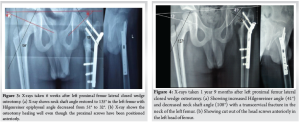

Magnetic resonance imaging (MRI) showed signal intensity changes in the left femoral neck. NSA of the left femur was 115°, with Hilgenreiner epiphyseal (HE) angle of 51° (Fig. 2), and hence, surgical correction was required [1,2,3,4].

On August 22, 2013, the patient underwent surgery: Left proximal femur lateral closed-wedge osteotomy. A wedge with a 1 cm base was removed at the corticotomy site, corresponding to a correction angle of 25° based on templating with a magnification marker (Fig. 2 – a K-wire of known length was used as a magnification marker). Closed biopsy was taken from the neck of the femur. Two cannulated cancellous screws were passed through the neck (not crossing the physis) and locked to the prebent 3.5 mm six-holed dynamic compression plate. Since the proximal femoral physis contributes to around 15% of the overall growth of the femur, the screws were fixed without crossing the physis [5]. The plate was fixed to the shaft with three cortical screws. Post-operatively, the NSA and HE angle were restored (Fig. 3).